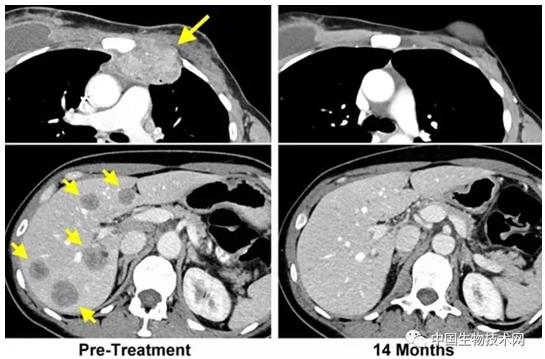

當時49歲的Perkins首先是接受了化療來阻止右側乳房中的腫瘤繼續生長,但是以失敗告終。之后她被選擇接受這種新型療法。期間,腫瘤還擴散到了她的肝臟和其他部位,這也是醫生們決定對她進行免疫治療的決定因素之一。幸運的是,治療結果非常成功:她體內的癌細胞被完全清除了,即使兩年后,醫生們也沒有在她體內發現癌細胞的蹤跡。這是該方法首次取得成功。根據NCI外科主任Steven Rosenberg的說法,研究人員在過去曾經利用該技術使六位罹患結腸癌或宮頸癌患者難以治療的腫瘤縮小了。